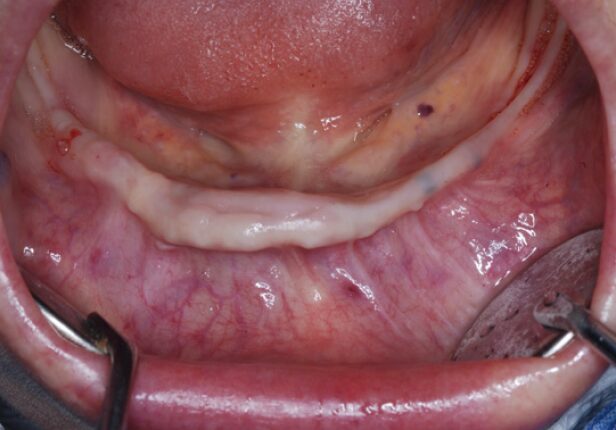

Antes da cirurgia

caso de estudo

Antes da colocação da coroa final